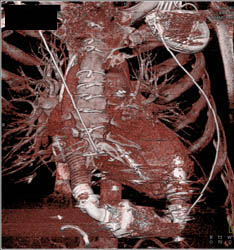

Normal Coronary Artery Anatomy